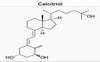

Draw Vit D synthesis

Where does 25-hydroxylation occur?

1-hydroxylation?

Liver

Kidney

What proportion of absorbed vit D is hydroxylated at the 25 position?

What enzyme?

What is the activity of this?

100%

25 hydroxylase

Inactive, stored and measured form of Vit D